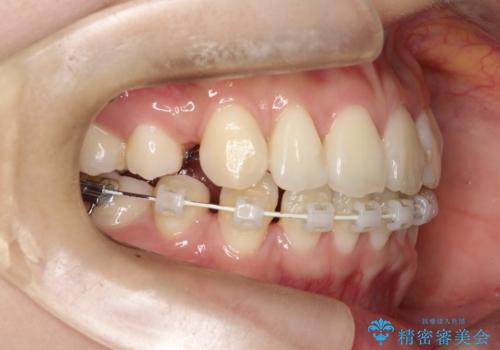

- 出っ歯、ガタツキ、噛み合わせが気になるとのことで来院された患者様です。

小臼歯を抜歯することでスペースを作り、前歯を下げて口元を下げ、Eラインを改善する治療方針としました。

表側のワイヤーは見た目が気になるとのことで、上の歯だけ裏側に付くハーフリンガルという装置で治療を行いました。